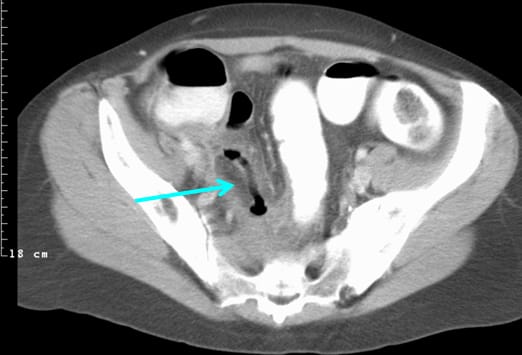

Es ist eine entzündlich veränderte und verdickte Appendix mit einem Appendikolithen zu sehen (Pfeil). Die Diagnosestellung einer Appendizitis ist sicherer und kosteneffektiver, wenn bildgebende Verfahren eingesetzt werden. [1] Die Computertomographie (CT) des Abdomens ist die am häufigsten durchgeführte Untersuchung, wenn es um die Abklärung einer abdominellen Schmerzsymptomatik geht. Die Abdomenübersicht hat eine geringe Spezifität und Sensitivität. Die Abdomensonographie kommt vor allen bei Kindern zum Einsatz; allerdings ist ihre Aussage sehr stark Untersucher-abhängig. Das Mehrzeilen-CT zeigt eine hohe Sensitivität (98,5%) und Spezifität (98%), bei einer falsch-negativen Rate von <1% und einer falsch-positiv Rate von ~6%.[2]